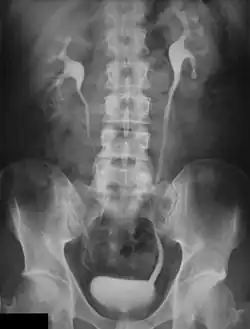

Uma imagem radiológica do sistema urinário.

Urografia excretora, urografia retrógrada, pielograma intravenoso ou pielografia são procedimentos radiológicos utilizados para observar as anormalidades do sistema urinário, incluindo os rins, ureteres, bexiga urinária e uretra.[1]